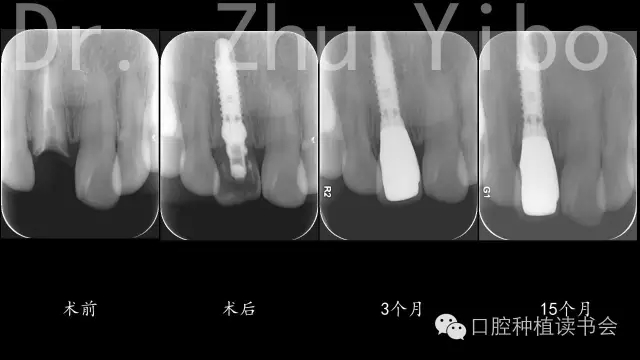

5、術(shù)后拍根尖片,確認臨時冠就位良好(圖12)。

640.webp (8).jpg

圖12

8、戴最終修復體,就位良好(圖12)。 術(shù)后1年復查,牙冠完好,牙齦美學評分14分(圖10、11)。

640.webp (12).jpg

術(shù)前術(shù)后CBCT對比測量示:唇側(cè)牙槽骨穩(wěn)定(圖13)。術(shù)前術(shù)后石膏模型掃描,數(shù)字軟件重合對比測量:唇側(cè)牙齦組織穩(wěn)定(圖14)。